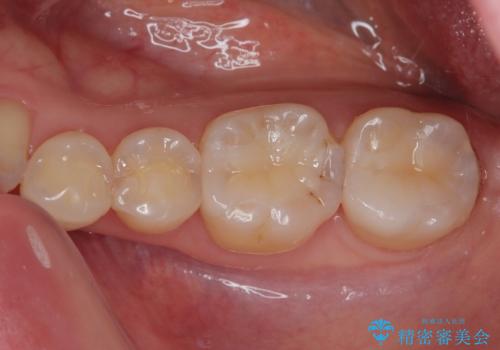

- 銀歯がとれたのでやり替えたいとのことで来院された患者様です。来院時特に症状もなく金属の詰め物(メタルインレー)がとれたのでセラミックの詰め物(セラミックインレー)にやり替えていくことになりました。また患者様のご希望によりひとつ後ろの歯の金属の詰め物(メタルインレー)のやり替えも同時に治療していくことになりました。

歯と歯の間の虫歯をコンポジットレジンや保険のメタルインレーで治すと段差ができたりして清掃性が悪くなるので、セラミックインレー修復やゴールドインレー修復などの適合の良い詰め物で治療することをオススメします。